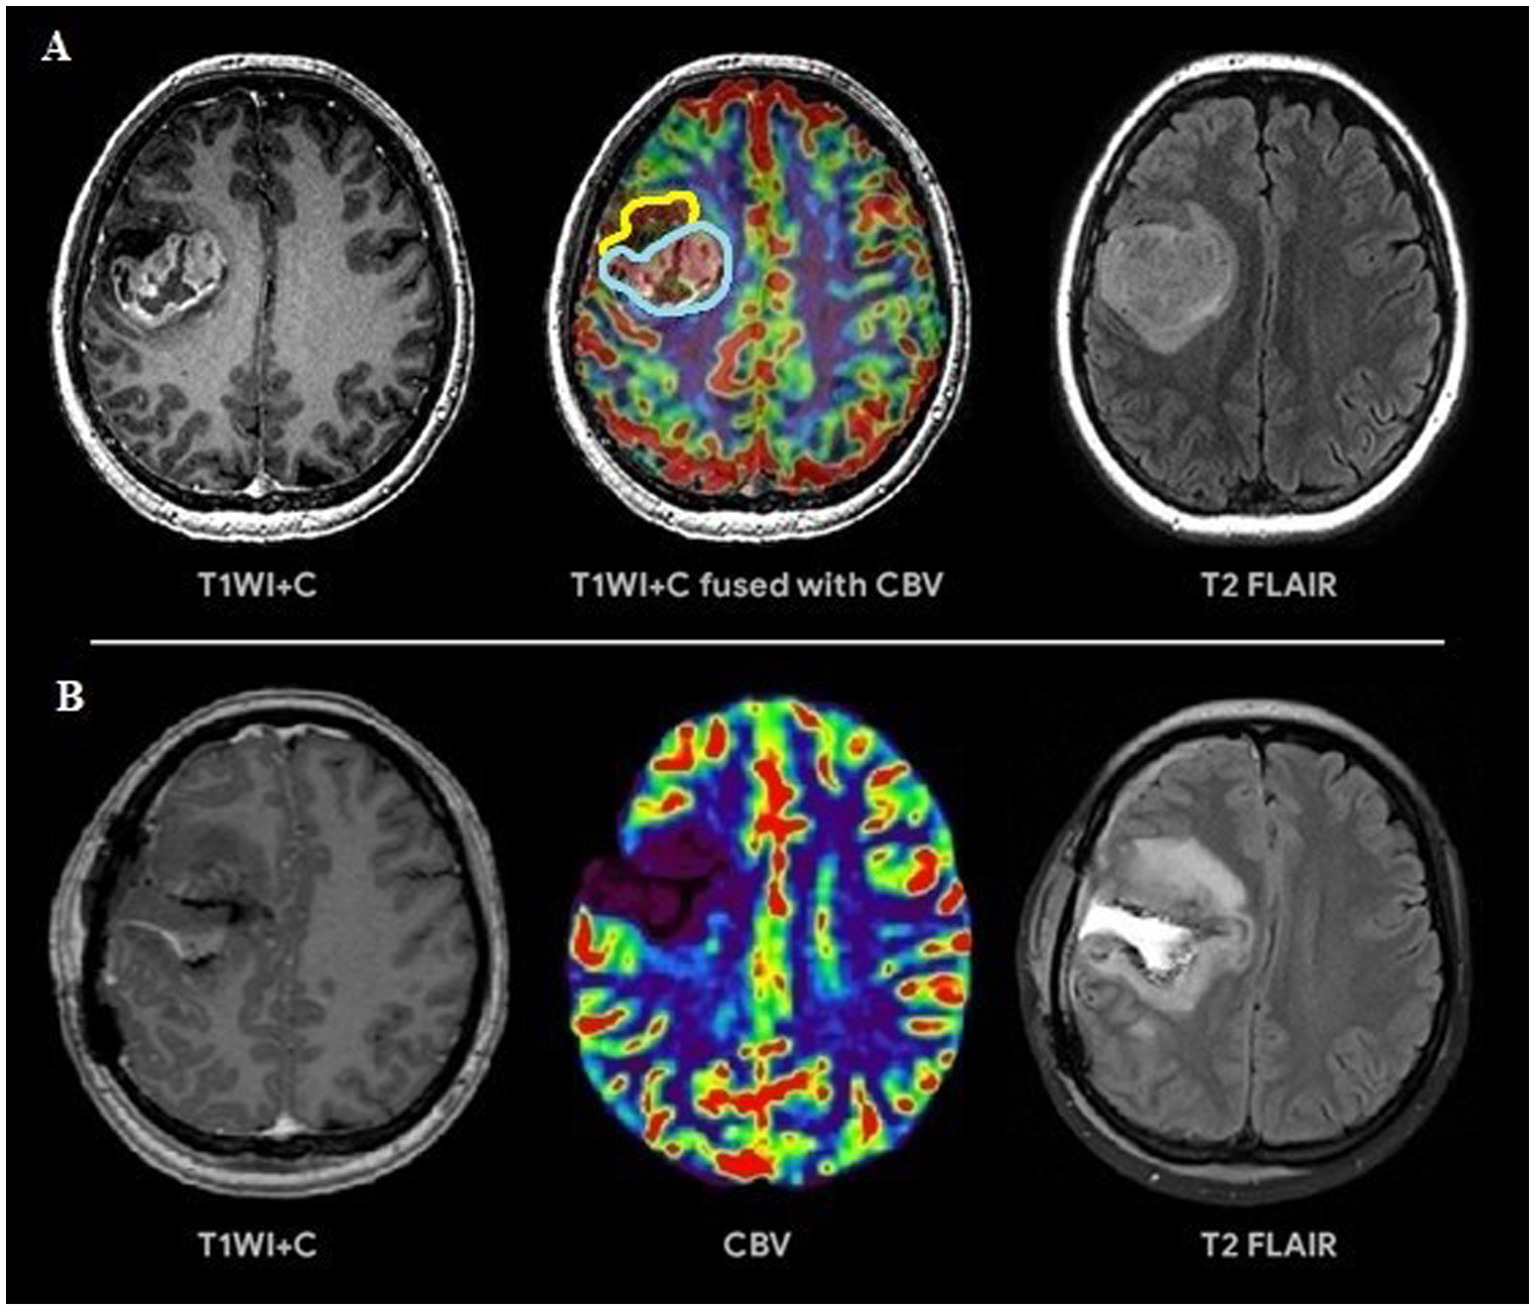

Based on the conducted research the following results were obtained. Group 1 including 42 patients (56.7%; Figure 3) had a surgical resection of the contrast-enhancing and hyperperfused portions of the tumor (total resection), Group 2 including 32 people (43.3%; Figure 4) had a surgical resection of only the contrast-enhancing part of the tumor (subtotal resection).

Figure 3

(A) Preoperative tumor resection planning in 42-years old patient with glioblastoma with regard to comparison of post-contrast T1 series, CBV parameter obtained using DSC-T2* perfusion and T2-Flair. The tumor has 2 portions: contrast-accumulating (blue line) and contrast-negative with high CBV volume (yellow line), which correspond to each other. (B) Postoperative MRI control 24 h after operation, post-contrast T1 series, CBV indicator obtained during DSC-T2* perfusion and T2-Flair. MRI data reveal resection of the contrast-accumulating component and the component with high CBV values and non-accumulating contrast agent; a zone of perifocal edema-infiltration is visualized in T2-Flair.